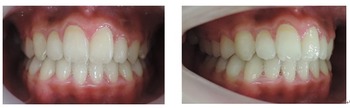

☆初診時

当矯正歯科医院では、まず上顎骨の劣成長の改善から治療を始めていきます。

出来るだけ目立たない矯正装置を使って上顎骨の拡大を始めます。

金属の矯正装置がありますが、これは隣の歯との段差が大きい場合に使用します。

3ヶ月ぐらいで矯正装置は全て小さな目立たない装置になりました。

咬合高径の改善、前歯の審美的改善のためにMEAW法(マルチループ)を使用しています。

☆治療終了時

永久歯を抜歯する事無く治療を完了する事が出来ました。